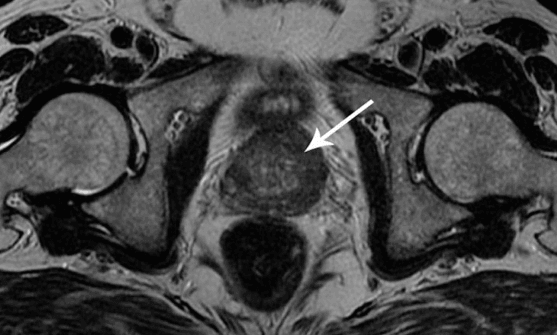

Ich möchte Ihnen ein paar Fotos zeigen, um zu zeigen, was im Urogenitalsystem und anderen Organen eines Mannes vor sich geht, der keinen Sex hat.

So sieht eine Entzündung der Prostata aus, die durch Stagnation der Spermien verursacht wird (wenn die Hoden nicht geleert werden). Eine anhaltende Entzündung führt zuerst zu einem Prostataadenom und dann zu Krebs. Dies ist eine unvermeidliche Folge von Prostatitis, daher wird es als "Krankheit der älteren Generation" bezeichnet.